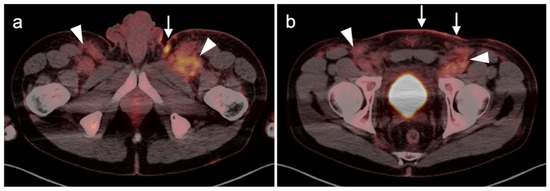

2.4. Merkel Cell Carcinoma

2.5. Cutaneous Squamous Cell Carcinoma